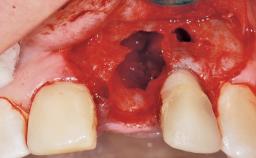

Immediate Flapless Placement of an Implant in a Maxillary Left Central Incisor Site

A 29-year-old female patient presented for treatment to replace the upper left central incisor tooth with an implant- supported restoration. The tooth had been intermittently symptomatic for the previous 12 months. The tooth had originally suffered trauma about 15 years previously. Several endodontic treatments had been performed, including an apicectomy procedure to retain the tooth. The patient was healthy and a non-smoker. She had reasonable expectations in regard to esthetic outcomes and the risk of marginal tissue recession following treatment. At medium smile, the gingival margins of the upper teeth were visible, with a display of 3 to 4 mm of the gingival margins. Gingival recession of tooth 21 and a discrepancy in the gingival levels between teeth 11 and 21 was observable during normal speech and smile.